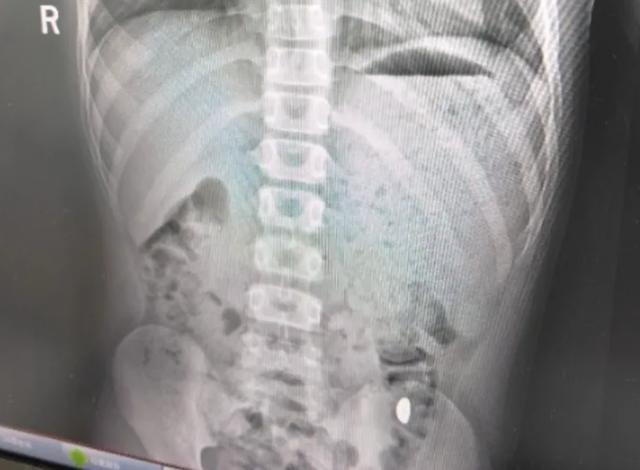

右下加亮点为金豆